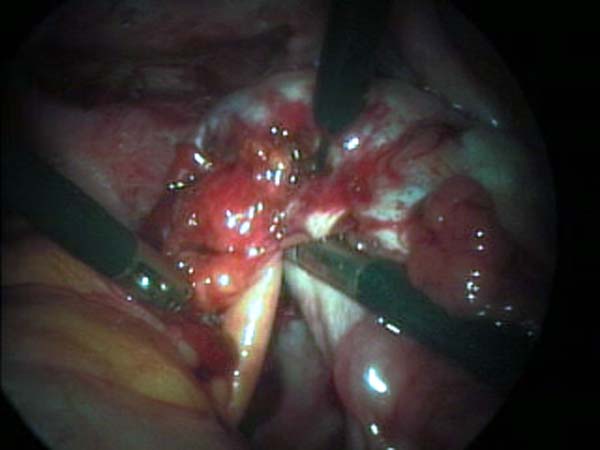

- Laparoscopy Photos 1

- Laparoscopy Photos 2

- Laparoscopy Photos 3

- Laparoscopy Photos 4

Laparoscopy Photos Polycystic Ovaries adhesiolysis IUCD Through Uterine Wall | Dr N Layyous